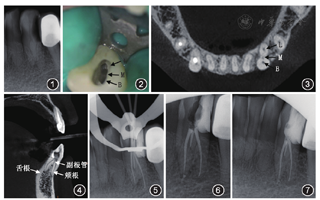

患者女性,55岁。主诉:左下前牙疼痛3 d。左下前牙龋坏1年余,偶尔伴冷热刺激不适,未治疗。现自发性、阵发性钝痛3 d,求治。患者否认高血压、心脏病、糖尿病等系统性病史,否认药物过敏史。临床检查:33远中邻唇面龋,叩诊(+),无松动,牙龈无明显异常,牙髓冷测试敏感。根尖X线片示33牙冠远中大面积近髓低密度影像,牙根呈双根影像,根尖区骨质无明显异常(图1)。诊断:33慢性牙髓炎。治疗计划:①33根管治疗术;②冠修复。处理:患者签订知情同意书。常规消毒,局部麻醉下去腐备洞,树脂制备远中假壁,上橡皮障。显微镜下开髓,超声清理髓室,探针初步探查到颊舌向2个根管口,通畅根管,根尖定位仪测得根管长度颊侧较舌侧长6 mm,结合术前X线片,确定舌侧还有1个根管,继续舌向磨除部分牙体组织,探查到舌侧根管,测得该根管长度略小于颊侧根管。预备至30号0.04锥度(图2)。因该牙根管系统较特殊,经患者同意封棉球后行锥形束CT检查。结果显示:水平面示唇舌向3个根管影像(图3);矢状面示双根双根管影像,髓室底至根分叉区可见一副根管影像(图4)。封氢氧化钙糊剂。

1周后复诊,患者未诉疼痛不适。33上橡皮障,试主尖并拍摄根尖X线片,显示牙胶尖达根尖部(图5)。根管充填,根尖X线片显示恰填(图6,图7)。1周后行冠修复。

对根管结构的充分掌握是根管治疗成功的重要基础。相比于后牙,前牙牙根及根管的变异率较低,临床上容易忽视,下颌前牙根管系统较上前牙复杂,因此在临床工作中容易因遗漏根管导致治疗失败。下颌尖牙多为单根单管,常见的变异为单根双根管,尖牙变异为双根较罕见[1,2,3]。本例患者的初诊X线片可见33呈双根影像,锥形束CT明确了牙根在根中1/2处分为颊根及舌根,即此病例为双根尖牙。尖牙的这种牙根变异可为单侧或双侧,本例患者的锥形束CT显示变异局限于左侧。

侧副根管、根尖分歧可能成为牙髓病与牙周病相互影响的通道,也增加了根管治疗的复杂性。副根管为发自髓室底至根分叉的管道,多见于磨牙。由于其直径较细小,临床上对副根管的预备及充填的报道较少。本例患者的尖牙变异为双根牙,在根分叉区有可能存在副根管,经锥形束CT确认,其根管始自髓室底终于根分叉区,为副根管。副根管是牙周牙髓交互的途径之一,也是药物渗漏及致病菌侵犯的可能通路,副根管的遗漏极易造成根分叉区病变,因此在临床工作中应时刻警惕侧副根管的存在。